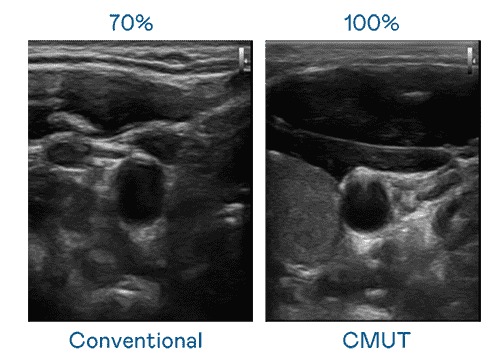

CMUT 技术是一种用电容式微机电元件来产生超音波讯号的技术。。与传统 PZT 压电式技术相比,,,CMUT 频宽增加 30%,,,更宽频的超音波讯号让影像解析度大幅提升,,,,是实现高影像品质医疗超音波扫描、、、、促进精准医疗发展的关键技术。。。。

大频宽带来超清晰影像

超音波影像的解析度高低,,,首先取决于探头能发出的讯号频宽。。。JDB电子 CMUT 可提供高清晰的超音波讯号,,,提供高频宽、、、、高灵敏度、、影像纹理细节更高的超音波影像,,,,协助医护人员缩短影像判读时间及利用精准的医疗影像进行诊断。。。